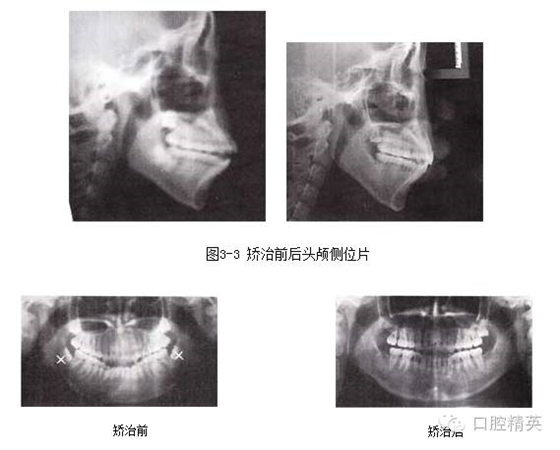

圖3-4 矯治前后全口曲面斷層片

1.前牙開(kāi)頜,伴有擁擠和輕度前突,上下前牙唇傾,拔除4顆前磨牙,可以解除擁擠,在內(nèi)收前牙的同時(shí),除了可以改善面型突度,通過(guò)“鐘擺效應(yīng)”可以加深覆頜。

2.下頜選擇拔除第二前磨牙,有利于調(diào)整磨牙關(guān)系由偏遠(yuǎn)中至標(biāo)準(zhǔn)中性。

4.阻生第三磨牙的拔除對(duì)于開(kāi)頜的矯治效果及療效的穩(wěn)定十分關(guān)鍵。

5.開(kāi)頜患者通常會(huì)伴有后牙的近中傾斜,MEAW技術(shù)的應(yīng)用可以壓低并直立磨牙,有利于開(kāi)頜的矯治。在MEAW使用過(guò)程中,需要將第二磨牙納入矯治序列。同時(shí)強(qiáng)調(diào)在前牙區(qū)使用垂直牽引。

6.矯治結(jié)束后,覆頜覆蓋正常,磨牙關(guān)系達(dá)到中性,后牙直立。